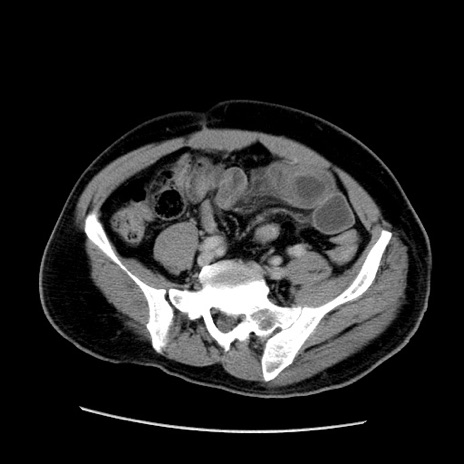

症例22(横断像)

【症例】50歳代男性

【主訴】腹痛

【現病歴】AVMからの被殻出血のため回復期リハ病棟入院中。 本日午後3時頃急に下腹部痛が出現した。

【既往歴】AVM、被殻出血、虫垂炎、高血圧

【身体所見】意識晴明、左半身不全麻痺、会話の理解は良好、36.5°C、腹部:膨隆、全体に板状硬、下腹部正中に圧痛点あり、反跳痛-、筋性防御不明、右下腹部にope scar

【データ】WBC 9400、CRP 0.06